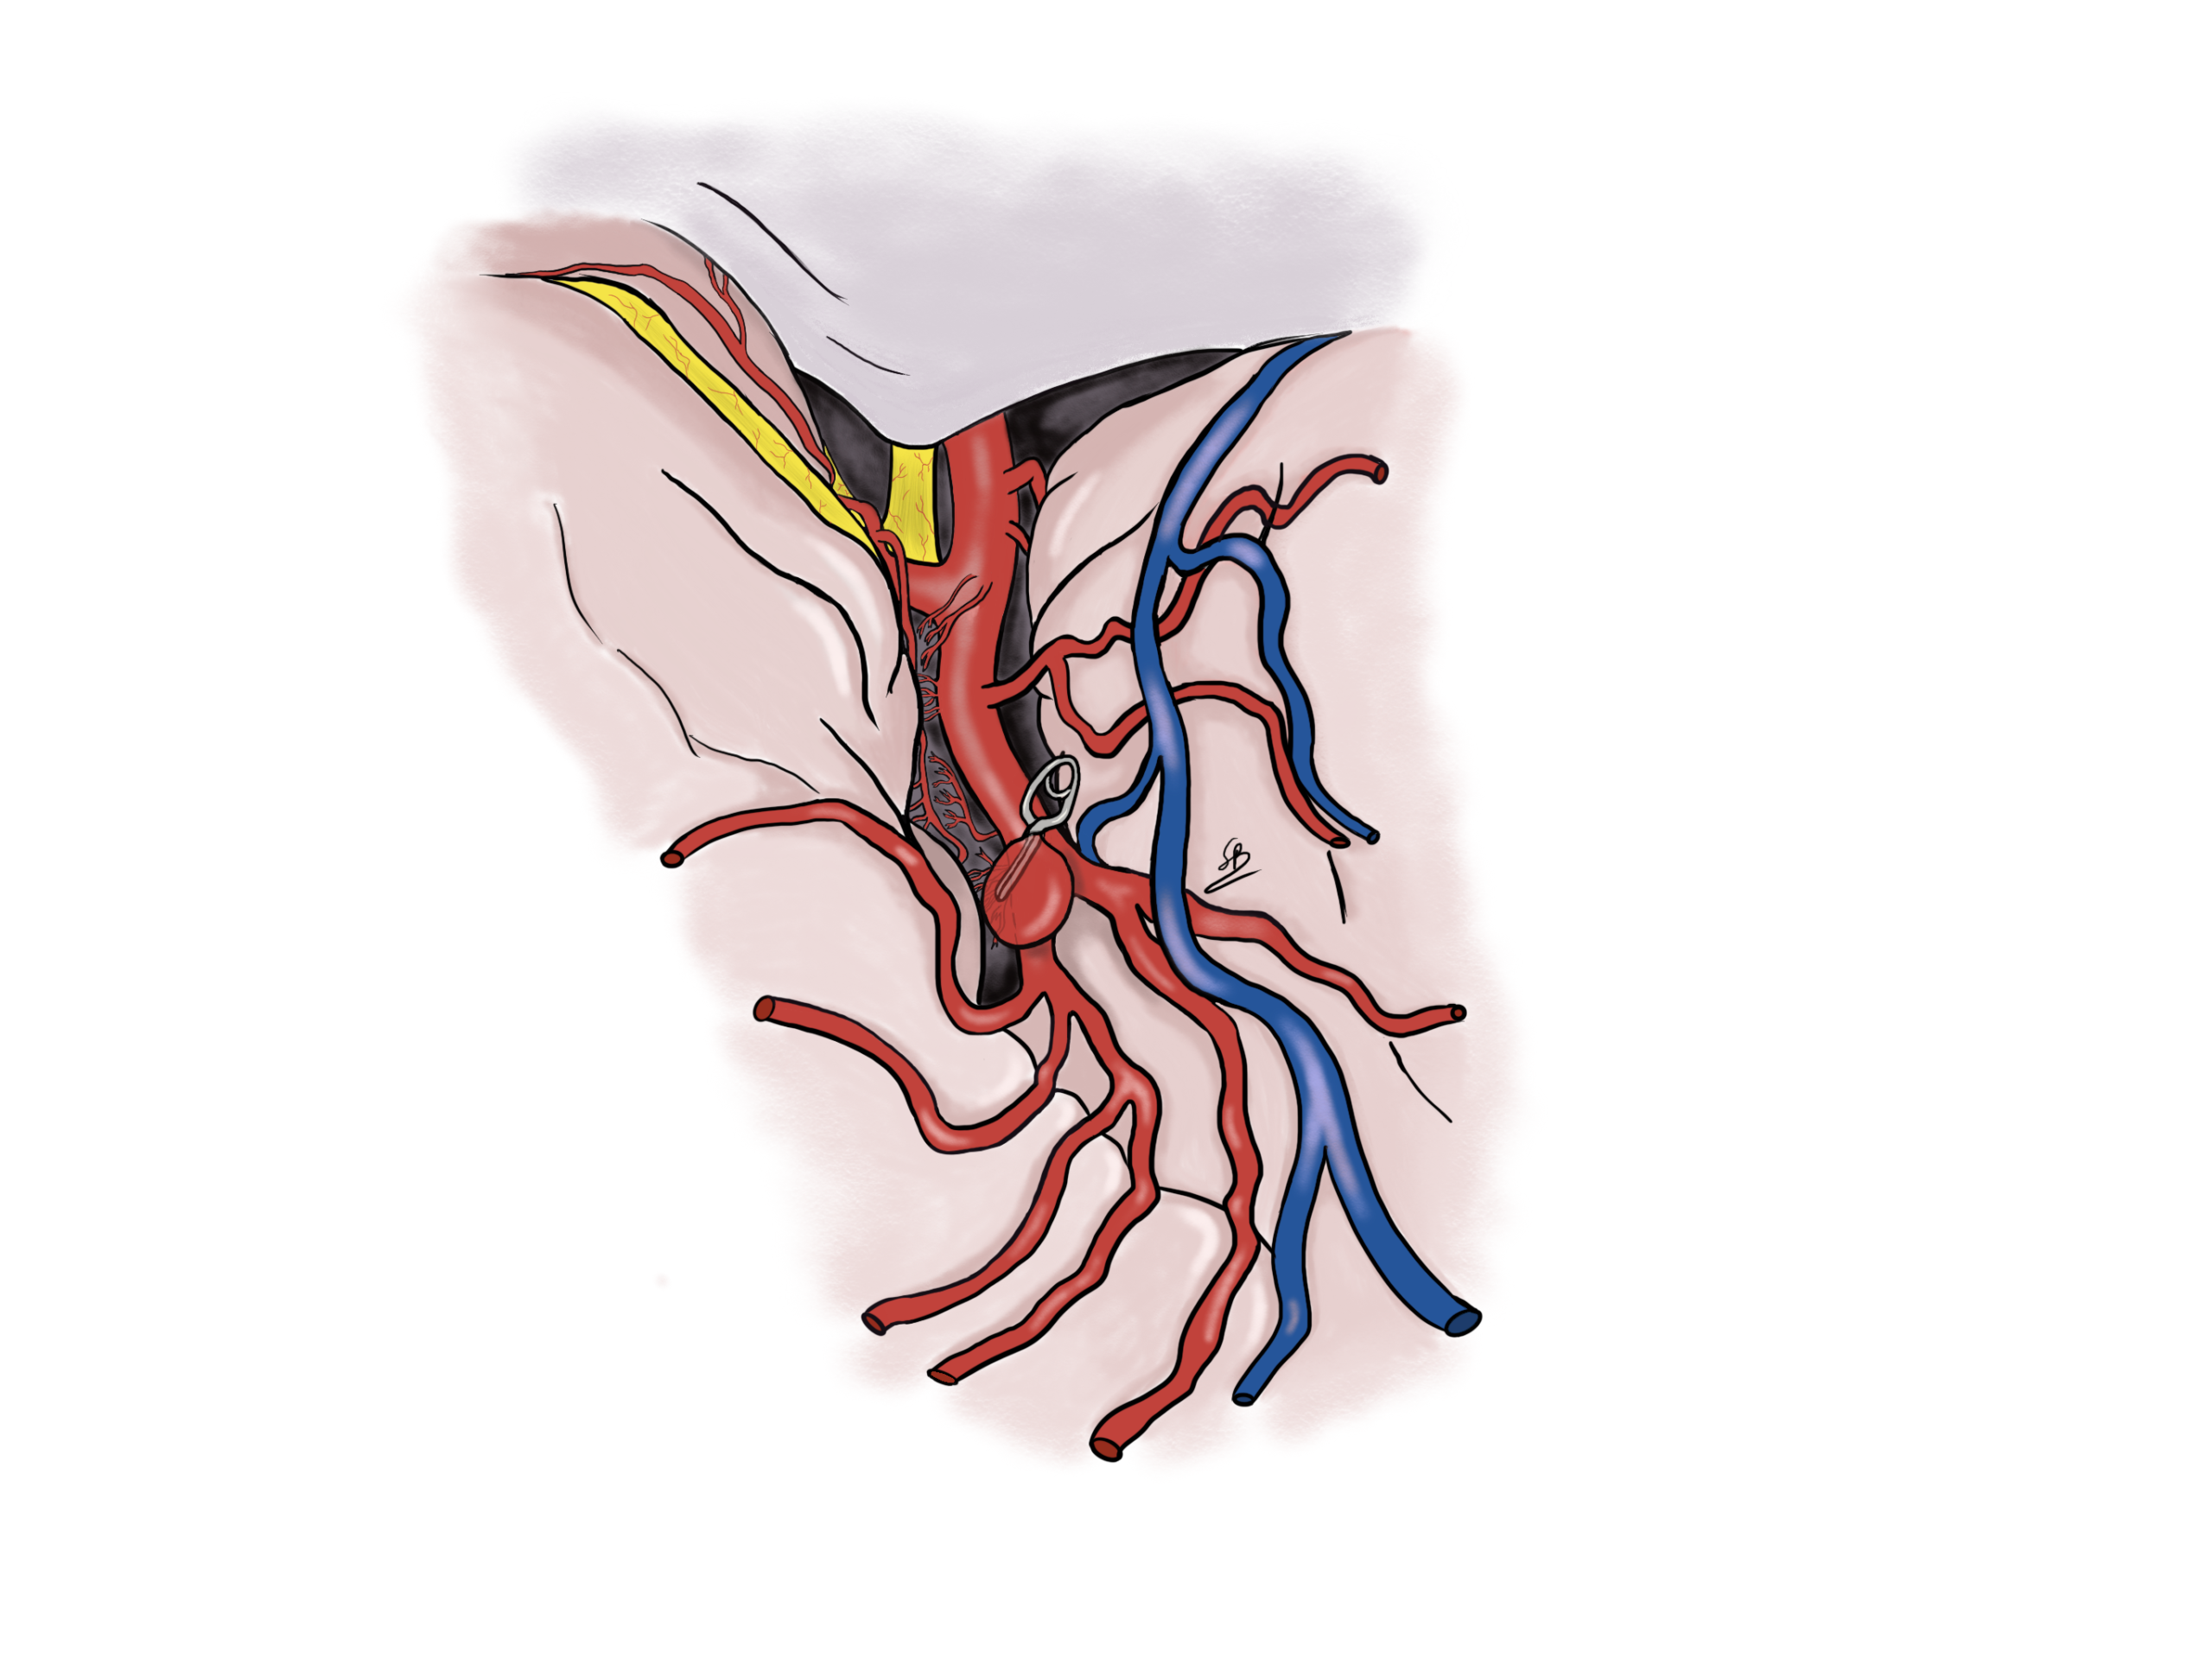

Clipping di un aneurisma

Esistono due trattamenti diversi per un aneurisma cerebrale: il clipping chirurgico ed il coiling endovascolare. Il Dr Robert e la dr.essa Bonasia hanno una grande esperienza nella presa decisionale e nei controlli degli aneurismi cerebrali. Sono specialisti per il clipping chirurgico degli aneurismi avendo realizzato più di 200 interventi di questo tipo. Si tratta di un trattamento che viene eseguito presso la Clinique La Source di Losanna.